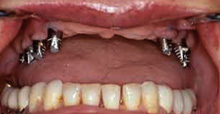

The regeneration of the jawbone is, in most cases, essential for implant placement. When a tooth is removed, the remaining bone atrophies. Atrophy increases with the years. This makes the placement of an implant difficult or impossible without first regenerating the bone

Our long experience in the regeneration of bone published in articles and dental conferances allowed us to recreate for our patients fixed dentitions instead of denture teeth.